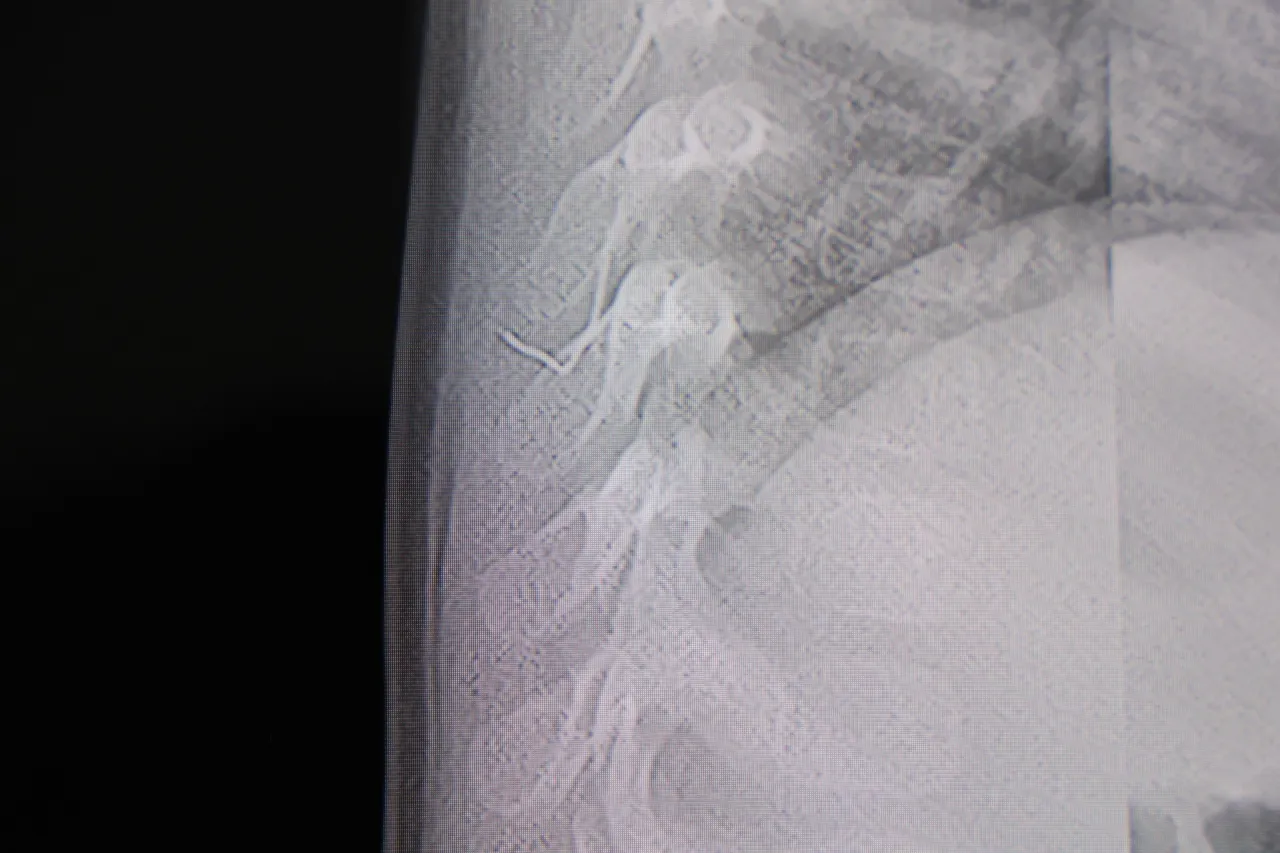

Yapılan ileri görüntüleme teknikleri sonucunda, yabancı cismin sadece cilt altında kalmadığı, omurilik kanalına çok yakın bir noktadan akciğer zarına doğru tehlikeli bir yol izlediği anlaşıldı. Zaman kaybedilmeden cerrahi müdahale kararı alındı.

Uzman ellerde gerçekleştirilen titiz çalışma neticesinde, bebeğin vücudundaki metal cisim tek parça halinde çıkarıldı. Yapılan incelemede, cismin yaklaşık iki santimetre uzunluğunda, ince bir zımba teli olduğu hayretle görüldü. Başarılı geçen operasyonun ardından sağlığına kavuşan bebek, ameliyatla aynı gün taburcu edildi.